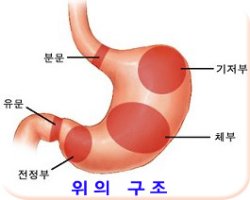

다.위암은 내시경 검사를 매년하자.

대장암은 나날이 증가추세이다.

내장내시경검사를 위하여 관장이 어렵고

부끄럽더라도 4-5년 간격으로 실시하자.

검사시 폴립은 무통으로 즉시 제거가 된다.